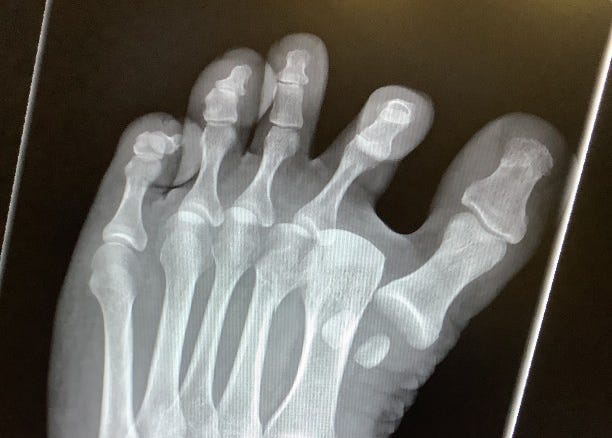

But I definitely have good reason to be significantly stronger than I am now. Because my wife and I live in a two-story house with five children, including a toddler. And this is an X-ray of my wife’s foot from three days ago.

The doctor reset her dislocated toe, but you may notice something we all missed in the emergency room: there’s a fracture in her second metatarsal. See if you can tell from the image. (No, it isn’t the pair of floating sesamoid bones at the lower right; they came back into alignment when they reset her toe. It was excruciating, but I gave her a candy bar afterwards, and she promised I would rue the day I dismissed her suffering was happy.)